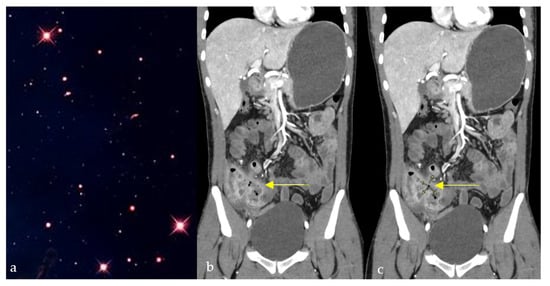

Cosmic Signs in Radiology: A Pictorial Review

Pattern recognition remains a cornerstone of radiologic interpretation, as it facilitates a confident and comprehensive differential diagnosis. Certain pathologies present with specific and highly recognizable patterns on imaging modalities. These patterns can resemble familiar real-life phenomena, including cosmic bodies that surround us. We present in this article a compilation of radiologic signs across various modalities that take inspiration from cosmic phenomena. For each sign, we summarize its defining imaging appearance, typical clinical context, and common pitfalls; where available, we note diagnostic performance (e.g., sensitivity/specificity) to guide appropriate weighting in practice. By coupling memorable imagery with succinct clinical guidance, this pictorial review aims to support a faster, more accurate pattern recognition that is applicable in both low-resource and tertiary care settings, while recognizing that these signs function as educational aids rather than validated diagnostic tests. In familiarizing themselves with these classic signs, training radiologists can benefit from an engaging and memorable way of recognizing various pathological conditions. Full article

Figure 1